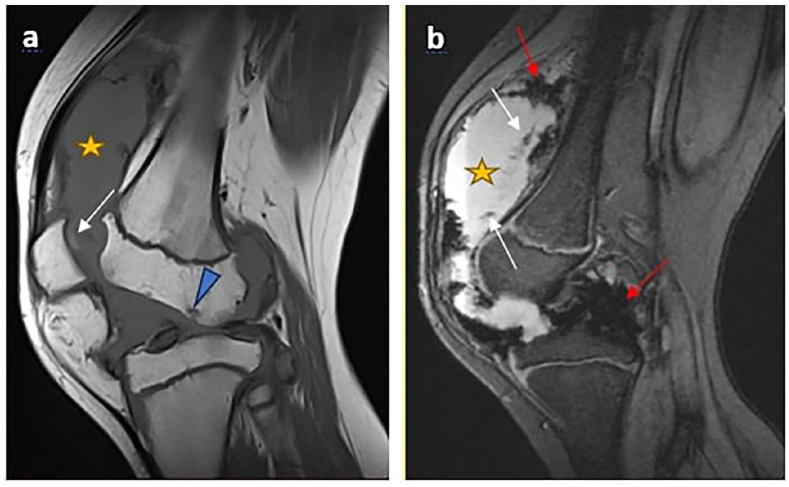

Hemophilia is a congenital coagulopathy characterized by a deficiency of coagulation factors and the development of haematomas and haemarthrosis, either spontaneously or after minor trauma. Recurrent joint hemorrhage in hemophilia patients leads to progressive and degenerative arthropathy, which affects around 90% of patients with severe disease and contributes significantly to disease morbidity. Positive diagnosis is based on biology. Imaging, particularly MRI, plays an essential role in assessing the evolution and complications, especially osteoarticular complications. We report 2 cases of severe hemophilia A, who presented with almost identical clinical and radiological symptoms. The patients developed severe arthropathy with a course marked by recurrences of haemarthrosis.

Abstract Image